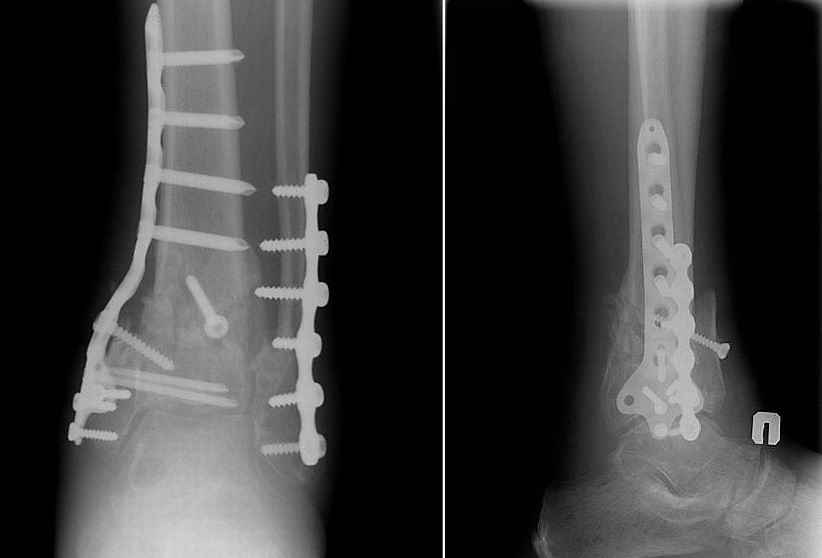

Re: Перелом пилона 6 мес. давности

Прооперировали 6 февраля.

На операции - несращение проксимального диафизарного отломка и осколков эпифиза, которые представляли собой неправильно сросшийся, крепкий конгломерат. С учетом сохранности движений в голеностопном суставе (боясь ему навредить), решено было не разбирать их, а только исправить ось голени, что и было сделано, после остеотомии и резекции малоберцовой кости + остеопластика.

Получилось видимо не идеально, внушает оптимизм хорошее состояние мягких тканей и сохранность движений в голеностопном суставе после операции. Хотя... :)